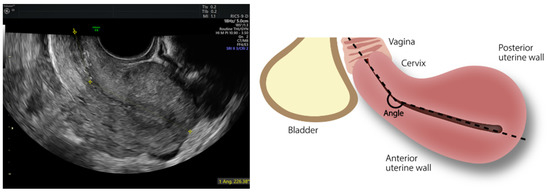

| Angle of flexion (°) | 146.1 ± 50.7 | 127.2 ± 38.2 | 157.5 ± 54.1 | 0.001 | |

| <150 | 90/120 (75.0%) | 39/44 (88.6%) | 51/76 (64.5%) | 0.004 | |

| 150–210 | 8/120 (6.7%) | 2/44 (4.5%) | 6/76 (7.9%) | 0.473 | |

| >210 | 22/120 (18.3%) | 3/44 (6.8%) | 19/76 (25.0%) | 0.015 | |